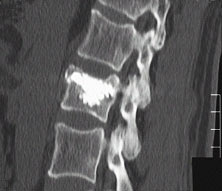

Bruch des 1. Lendenwirbelkörpers nach einem Sturz eines 60 jährigen Patienten

Abb. 6+7

Derselbe Patient nach Behandlung mittels percutaner Vertebroplastie. Zu erkennen ist die homogene Zementverteilung im Wirbelkörper (im Bild weiß). Der gebrochene Wirbelkörper konnte gut aufgerichtet werden. Ohne Bedeutung ist der geringe Zementaustritt aus dem Wirbelkörper